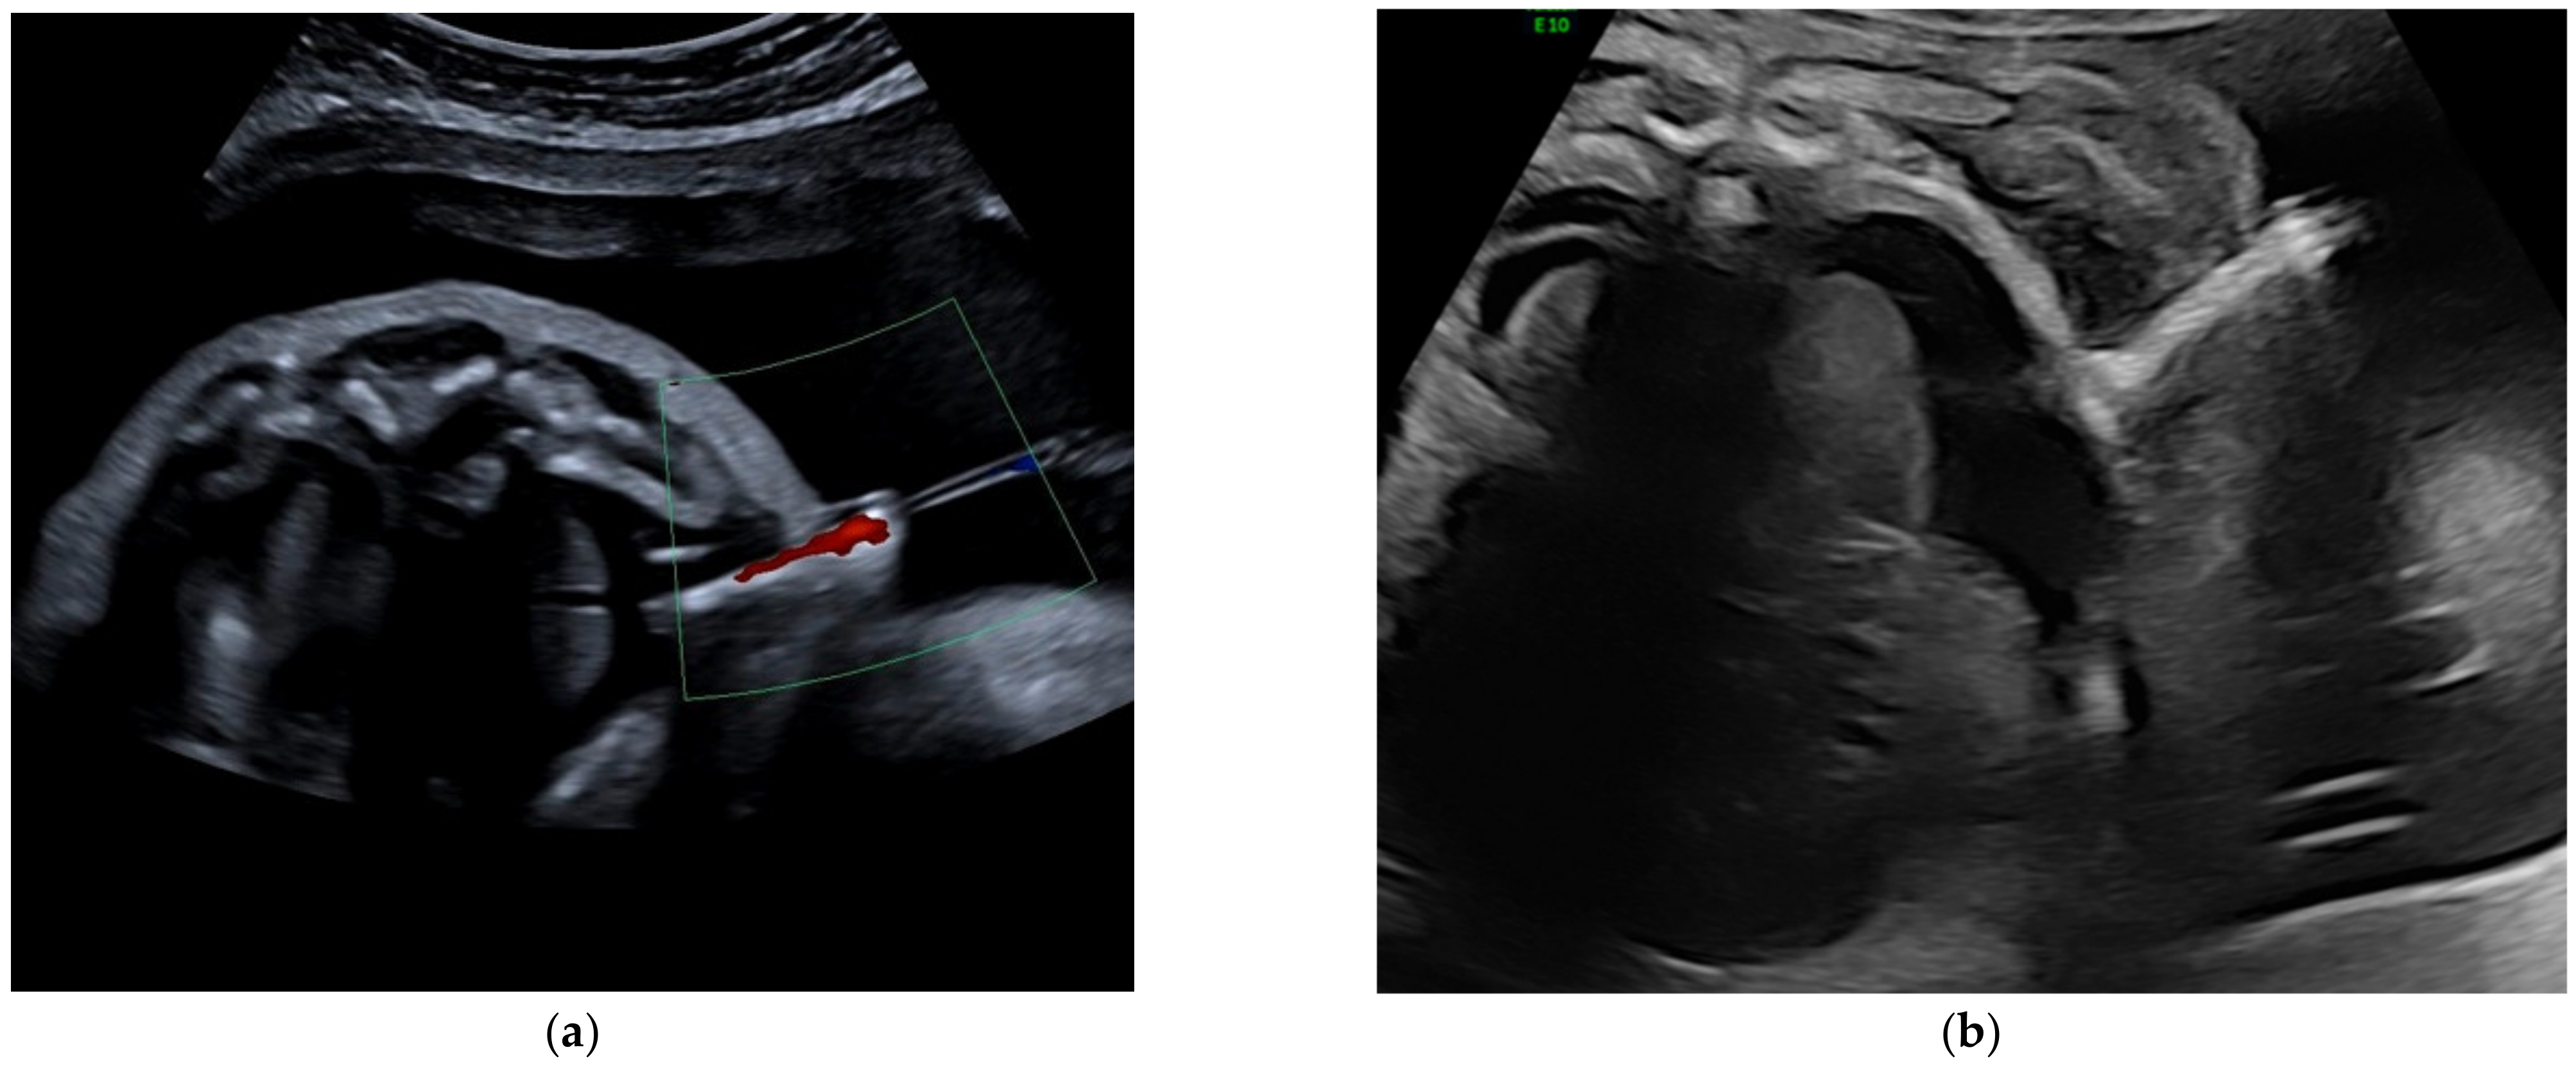

Figure 2. (a) Correct position of a Somatex shunt (axial view). Outward flow through the shunt is demonstrated by color Doppler. (b) Intracutaneous dislocation of a Somatex shunt in a fetus with massive skin edema on an axial view of the thorax. The inner end of the shunt is not reaching the pleural cavity.

Due to the small and retrospective design of our study, there are limitations. The small number of fetuses treated by very experienced physicians at a single center limits the generalizability of the results. On the other hand, it offers a unique opportunity to evaluate the outcome and complications of different shunt types, since mainly the same operators performed TAS during both study periods. However, even for those very experienced operators, correct placement of a Somatex shunt in the thorax seems to be more challenging compared to other shunt types, as approx. 30% of the procedures were difficult. To our knowledge, however, the rate of difficulties during shunt placement have rarely been reported in other studies. Interestingly, we did not observe this problem with the Somatex shunt for vesicoamniotic shunting (VAS). One difference is the gestational age at intervention, with VAS being performed earlier in pregnancy, mainly in the first or second trimester. Due to the advanced gestational age and polyhydramnios, fetal movements might impede TAS more. In addition, the length of the Somatex shunt is shorter (25 mm) compared to the Harrison shunt, which makes positioning fetuses with very thick skin edema more difficult (Figure 2). In view of the high complication rates of the Somatex shunt, technical improvements seems highly necessary.